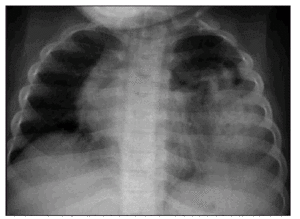

Radiografía de tórax: imagen de condensación que ocupa la mayor parte de hemitórax izquierdo (fig. 1). TC torácica: ocupación del hemitórax por contenido intestinal en región anterior que se extiende hasta ápice pulmonar (fig. 2). Diagnóstico: hernia de Morgagni de presentación tardía y hallazgo casual. Actualmente nuestra paciente está asintomática desde el punto de vista respiratorio y a la espera de la intervención quirúrgica.

Figura 2. TC torácica. Ocupación del hemitórax por contenido intestinal en región anterior del tórax, que se extiende desde las bases pulmonares hasta el vértice pulmonar.